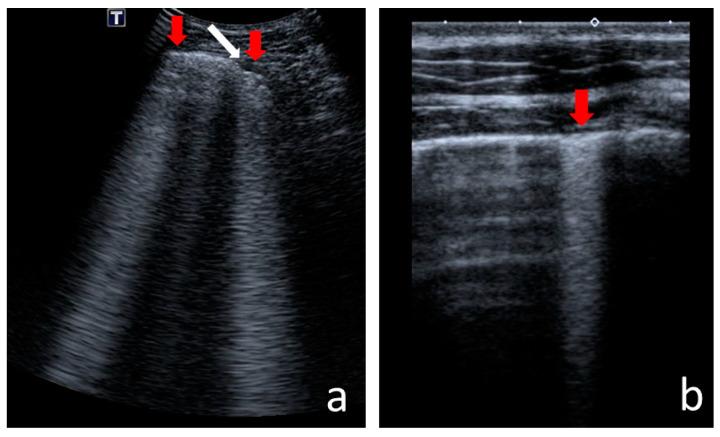

With the increasing longevity of cystic fibrosis (CF), there is a growing need to minimise exposure to ionising radiation in patients who undergo regular imaging tests while monitoring the course of the lung disease. This study aimed to define the role of lung ultrasounds (LUS) in the evaluation of lung disease severity in children with clinically stable CF. LUS was performed on 131 patients aged 5 weeks to 18 years (study group) and in 32 healthy children of an equivalent age range (control group). Additionally, an interobserver study was performed on 38 patients from the study group. In CF patients, the following ultrasound signs were identified: I-lines; Z-lines; single, numerous and confluent B-lines; Am-lines; small and major consolidations; pleural line abnormalities and small amounts of pleural fluid. The obtained results were evaluated against an original ultrasound score. LUS results were correlated with the results of chest X-ray (CXR) [very high], pulmonary function tests (PFTs) [high] and microbiological status [significant]. The interobserver study showed very good agreement between investigators. We conclude that LUS is a useful test in the evaluation of CF lung disease severity compared to routinely used methods. With appropriate standardisation, LUS is highly reproducible.

随着囊性纤维化(CF)患者寿命的延长,在对肺部疾病病程进行监测的同时,尽量减少接受常规影像学检查的患者所受电离辐射的需求日益增加。本研究旨在明确肺部超声(LUS)在评估临床病情稳定的CF患儿肺部疾病严重程度中的作用。对131例年龄在5周至18岁的患者(研究组)以及32例年龄范围相当的健康儿童(对照组)进行了LUS检查。此外,对研究组中的38例患者进行了观察者间研究。在CF患者中,识别出了以下超声征象:I线;Z线;单发、多发及融合的B线;Am线;小实变和大实变;胸膜线异常及少量胸腔积液。将获得的结果与原始超声评分进行对照评估。LUS结果与胸部X线(CXR)结果[高度相关]、肺功能测试(PFTs)结果[相关性高]以及微生物学状态[显著相关]相关。观察者间研究显示研究者之间具有很好的一致性。我们得出结论,与常规使用的方法相比,LUS在评估CF肺部疾病严重程度方面是一种有用的检查方法。通过适当的标准化,LUS具有高度可重复性。